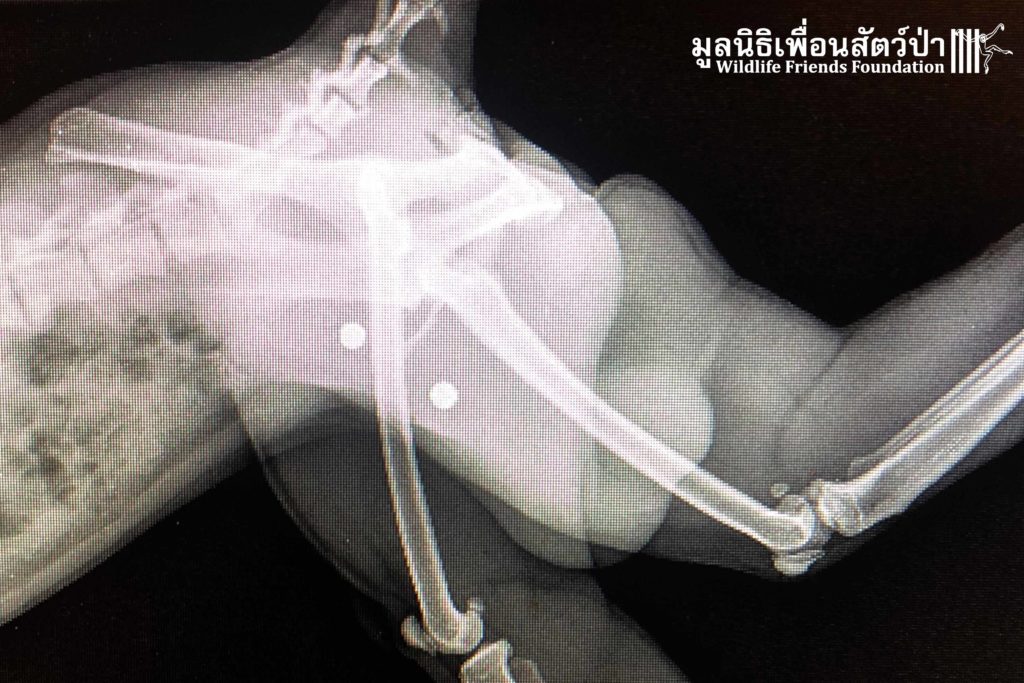

เมื่อทีมกู้ภัยไปถึงพบว่า เจ้าบันไดมีสภาพอ่อนเเอ ไม่เคลื่อนไหวเเต่ไม่มีบาดแผลให้เห็น จึงสันนิษฐานว่ามีกระดูกหักไม่ต่ำกว่า 1 ที่ เเต่เมื่อกลับมา x-ray ที่โรงพยาบาลสัตว์ป่า กลับพบว่าไม่มีร่องรอยหักใดๆ ทั้งสิ้น ทางทีมสัตวเเพทย์จึงคาดการว่าน่าจะได้รับการกระทบกระเทือนทางสมองส่งผลให้ไม่ตอบสนองต่อสิ่งเร้า นอกจากนั้นยังพบกระสุนอีก 2 นัดฝังอยู่บริเวณต้นขา

An x-ray was taken back at WFFT, it was found he has no fractured bones. He may have sustained a large impact to the head, which has caused some brain damage.